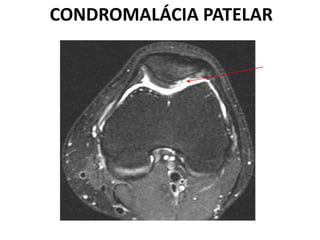

CONDROMALÁCIA PATELAR

 Lesão na cartilagem articular até a superfície óssea devido

ao excesso de forças de cisalhamento entre a patela e a

porção distal do fêmur.

 Comum em jovens e adultos.